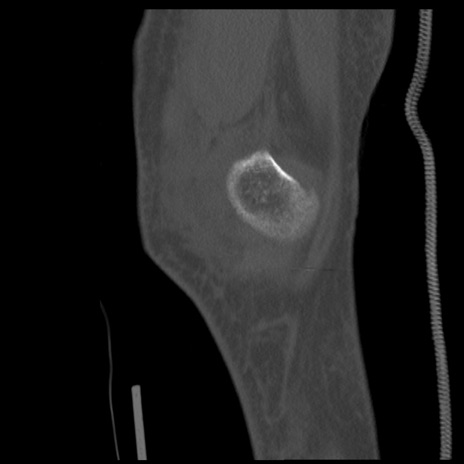

症例28 右膝関節CT(矢状断像)

右膝関節CT

横断像